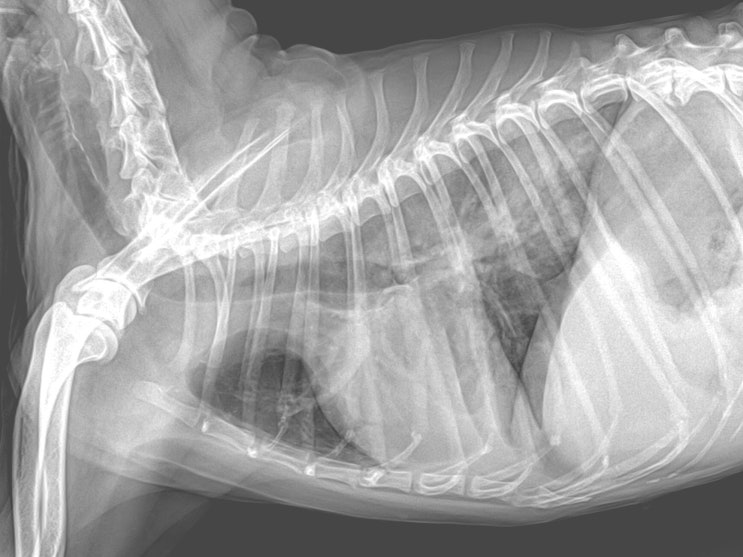

16살 푸들 강아지 폐수종 치료 후기 / 심장병 있는 댕댕이는 목욕도 조심하세요 / 반려견 미용 후 호흡 이상, 호흡수 상승 원인 / 노령견 심장병 치료 전문 동물병원

안녕하세요~ 굿파파 수의사입니다. 벌써 점심시간이 다가오네요~^^* 행복한 미소 가득한 하루 보내세요 오...